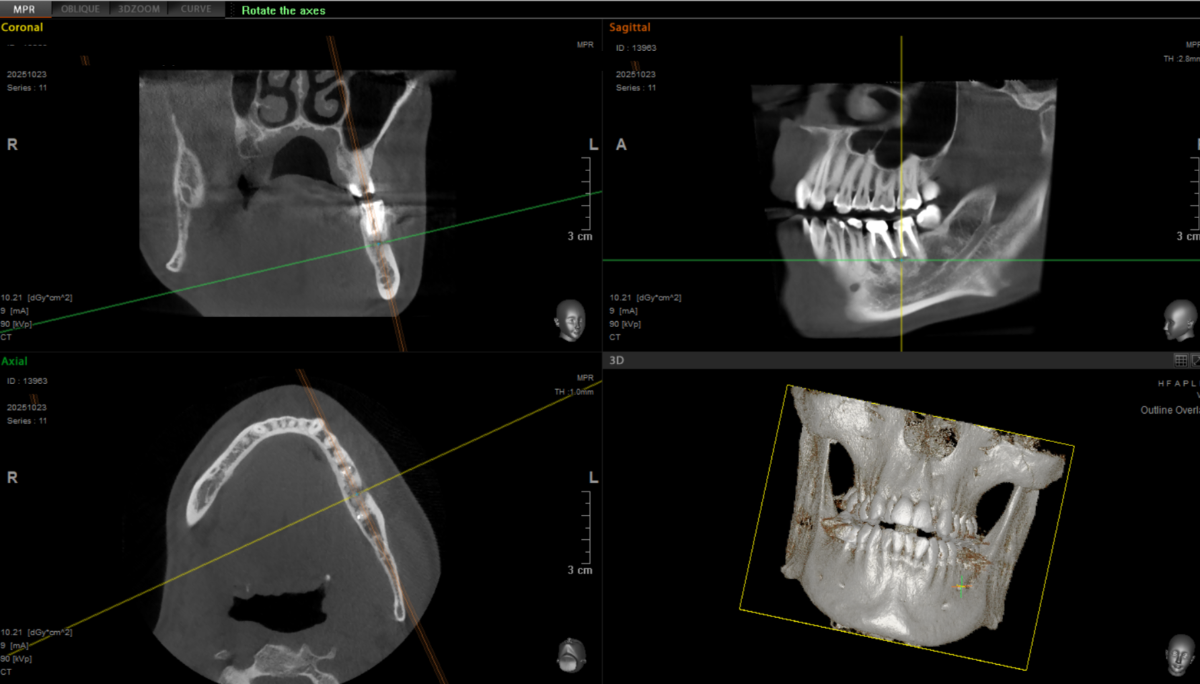

artek Опубликовано 20 декабря, 2024 Автор Поделиться Опубликовано 20 декабря, 2024 Всех приветствую. Прошло почти 5 лет с момента перелечивания. До прошлого года состояние кист было +/- стабильное, но последнее КТ показоло ухудшение. Выросла кисла на границе 6 и 5-го зуба. Врач, который занимался перелечиванием предложил, как вариант апекальную хирургию. Собственно вопрос, что порекомендуете делать в текущей ситуации? Ссылка на комментарий

artek Опубликовано 24 октября, 2025 Автор Поделиться Опубликовано 24 октября, 2025 Здравствуйте, товарищи стоматологи. Продолжаю борьбу за сохранение зубов. Сделал апекальную хирургию пол года назад и вчера контрольное КТ. Зубы продолжают периодически беспокоить, ощущения типа припухлости и легкого поднывания. Выделений и раздражений на десне визуально не наблюдаю, но по вкусу как будто что-то выходит из той области. Какие дальнейшие действия порекомендуете? Ссылка на комментарий